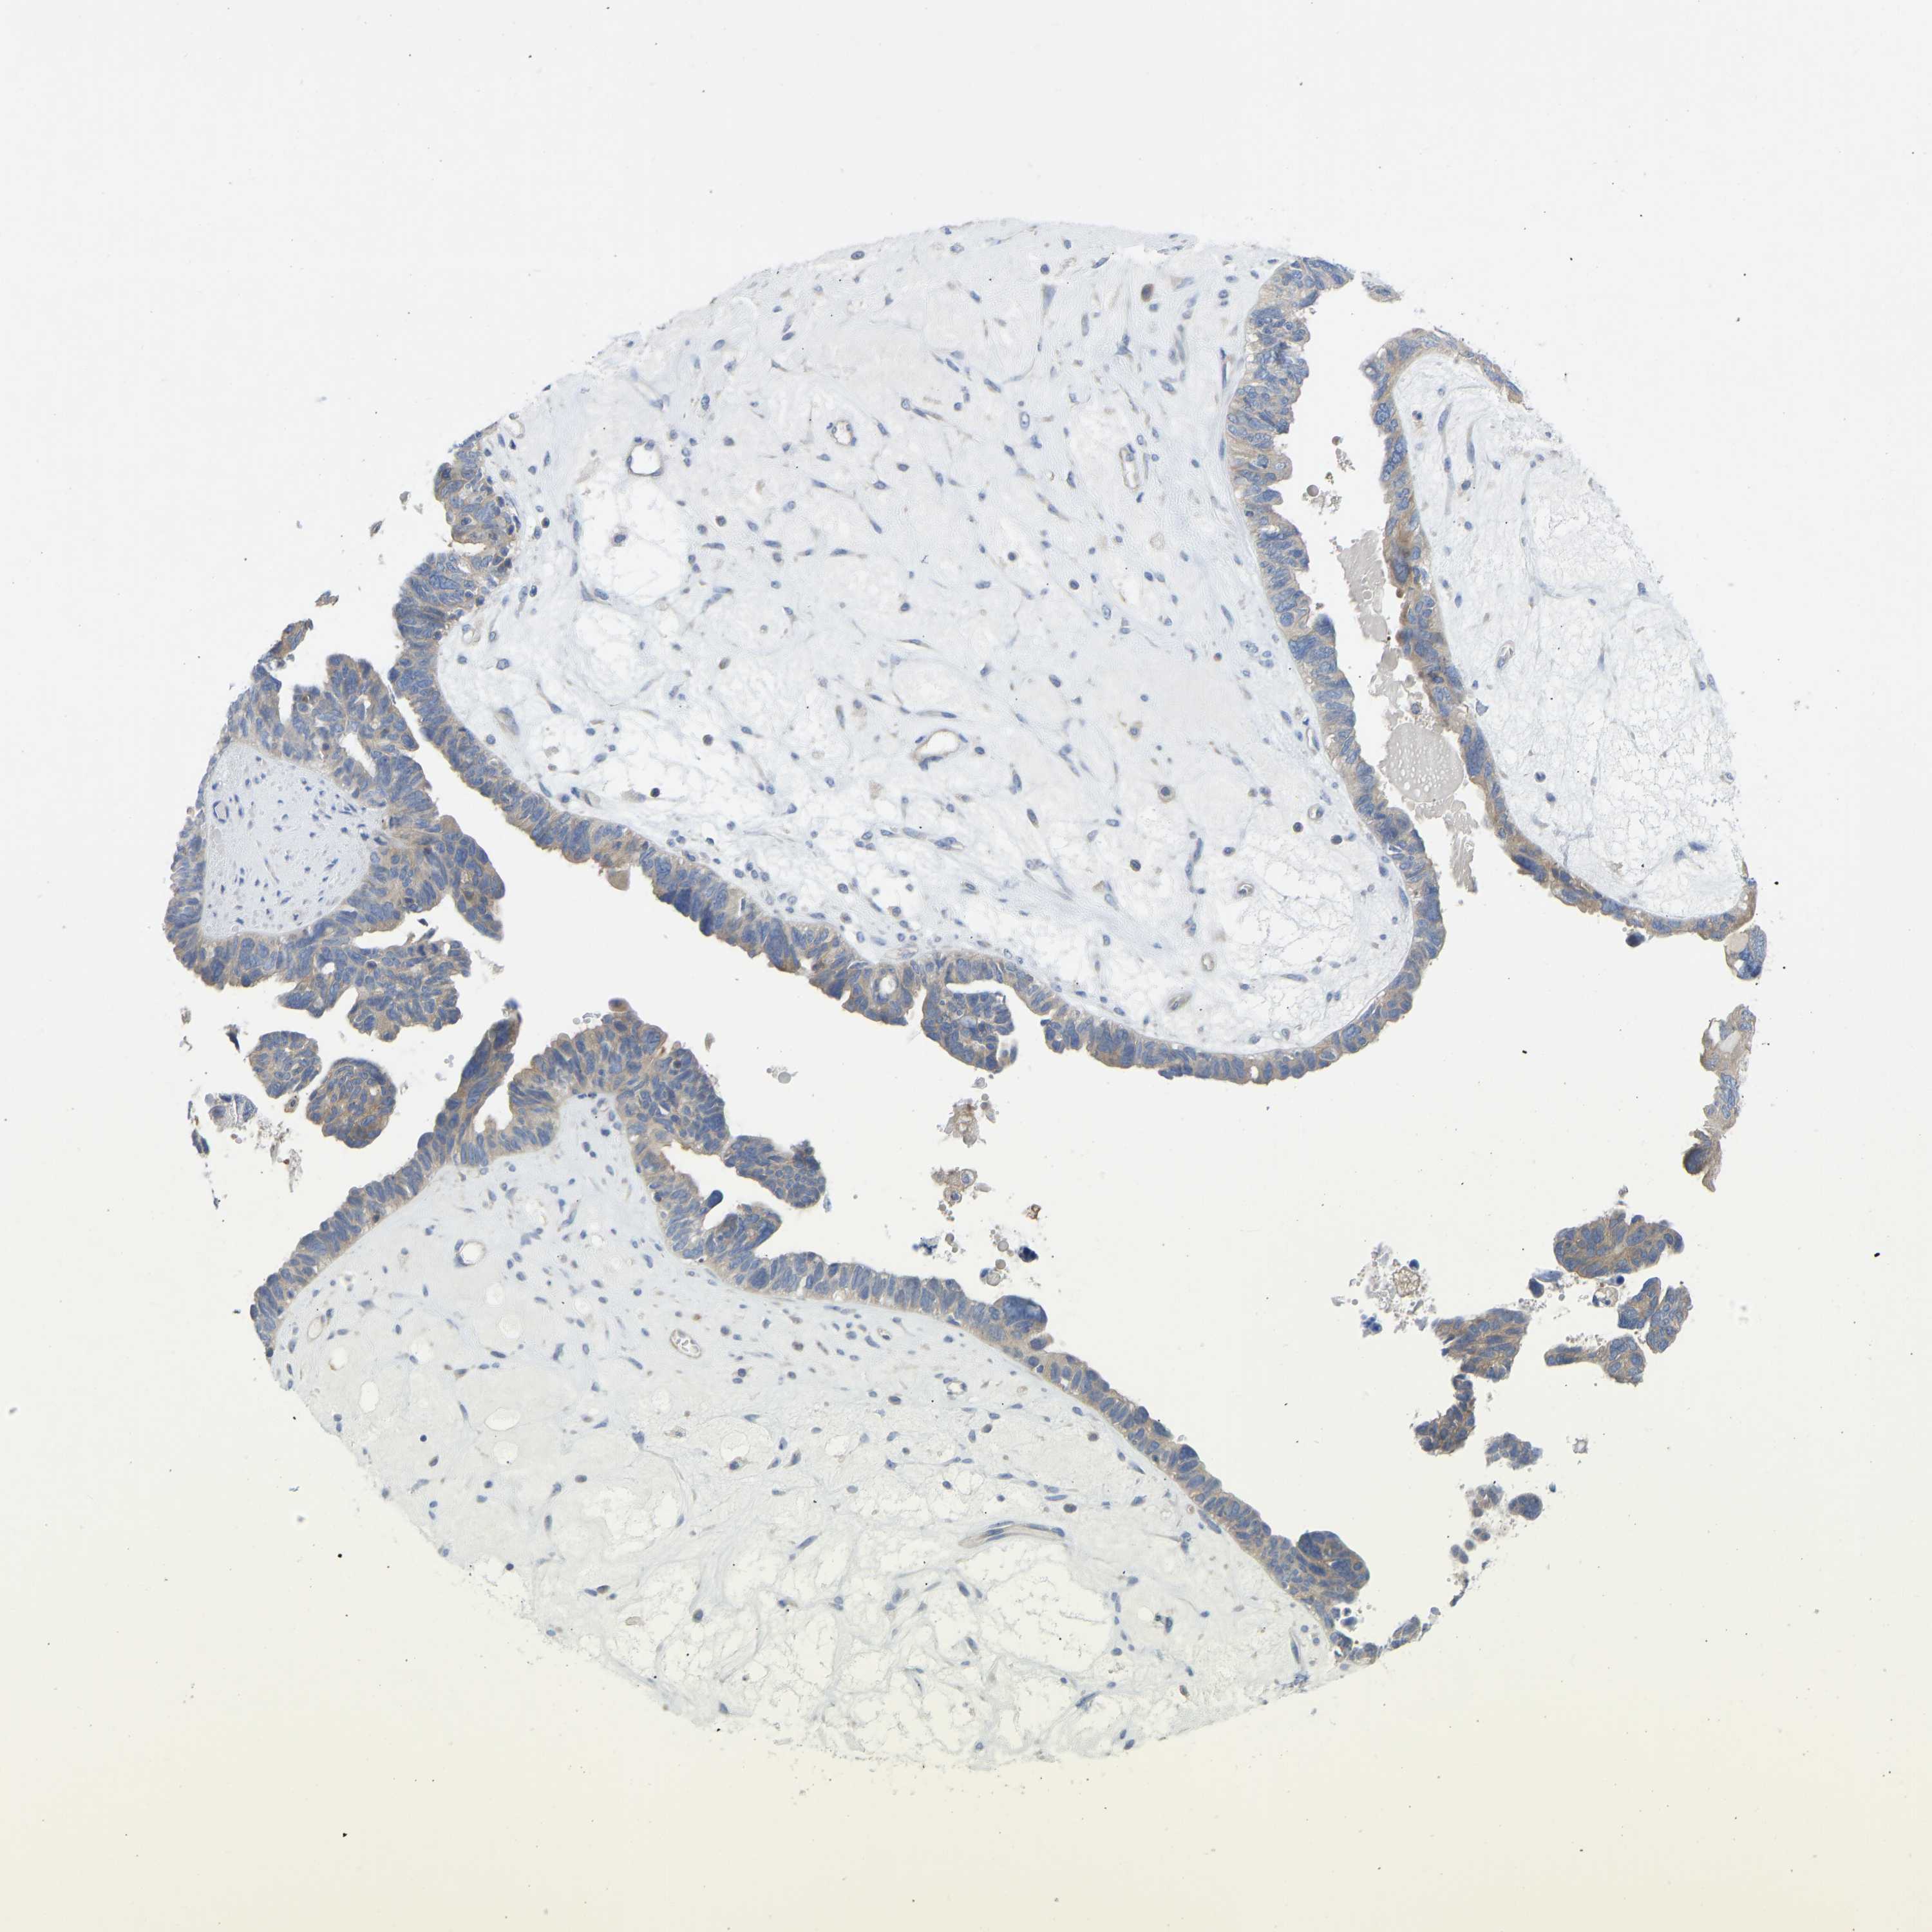

OVARIAN CANCER - Protein expressioni

A mouse-over function shows sample information and annotation data. Click on an image to view it in a full screen mode. Samples can be filtered based on level of antibody staining by selecting one or several of the following categories: high, medium, low and not detected. The assay and annotation is described here.

Note that samples used for immunohistochemistry by the Human Protein Atlas do not correspond to samples in the TCGA dataset.

Antibody stainingi

Antibody staining in the annotated cell types in the current human tissue is reported as not detected, low, medium, or high, based on conventional immunohistochemistry profiling in selected tissues. This score is based on the combination of the staining intensity and fraction of stained cells.

Each image is clickable and will lead to virtual microscopy that enables deeper exploration of all samples and also displays staining intensity scores, fraction scores and subcellular localization as well as patient and tissue information for each sample.

Antibody HPA012778

Antibody CAB018581

Staining

High

Medium

Low

Not detected

Intensity

Strong

Moderate

Weak

Negative

Quantity

>75%

75%-25%

<25%

None

Location

Nuclear

Cytoplasmic/membranous

Cytoplasmic/membranous,nuclear

Cystadenocarcinoma, serous, NOS

Carcinoma, endometroid

Cystadenocarcinoma, mucinous, NOS

Carcinoma, NOS